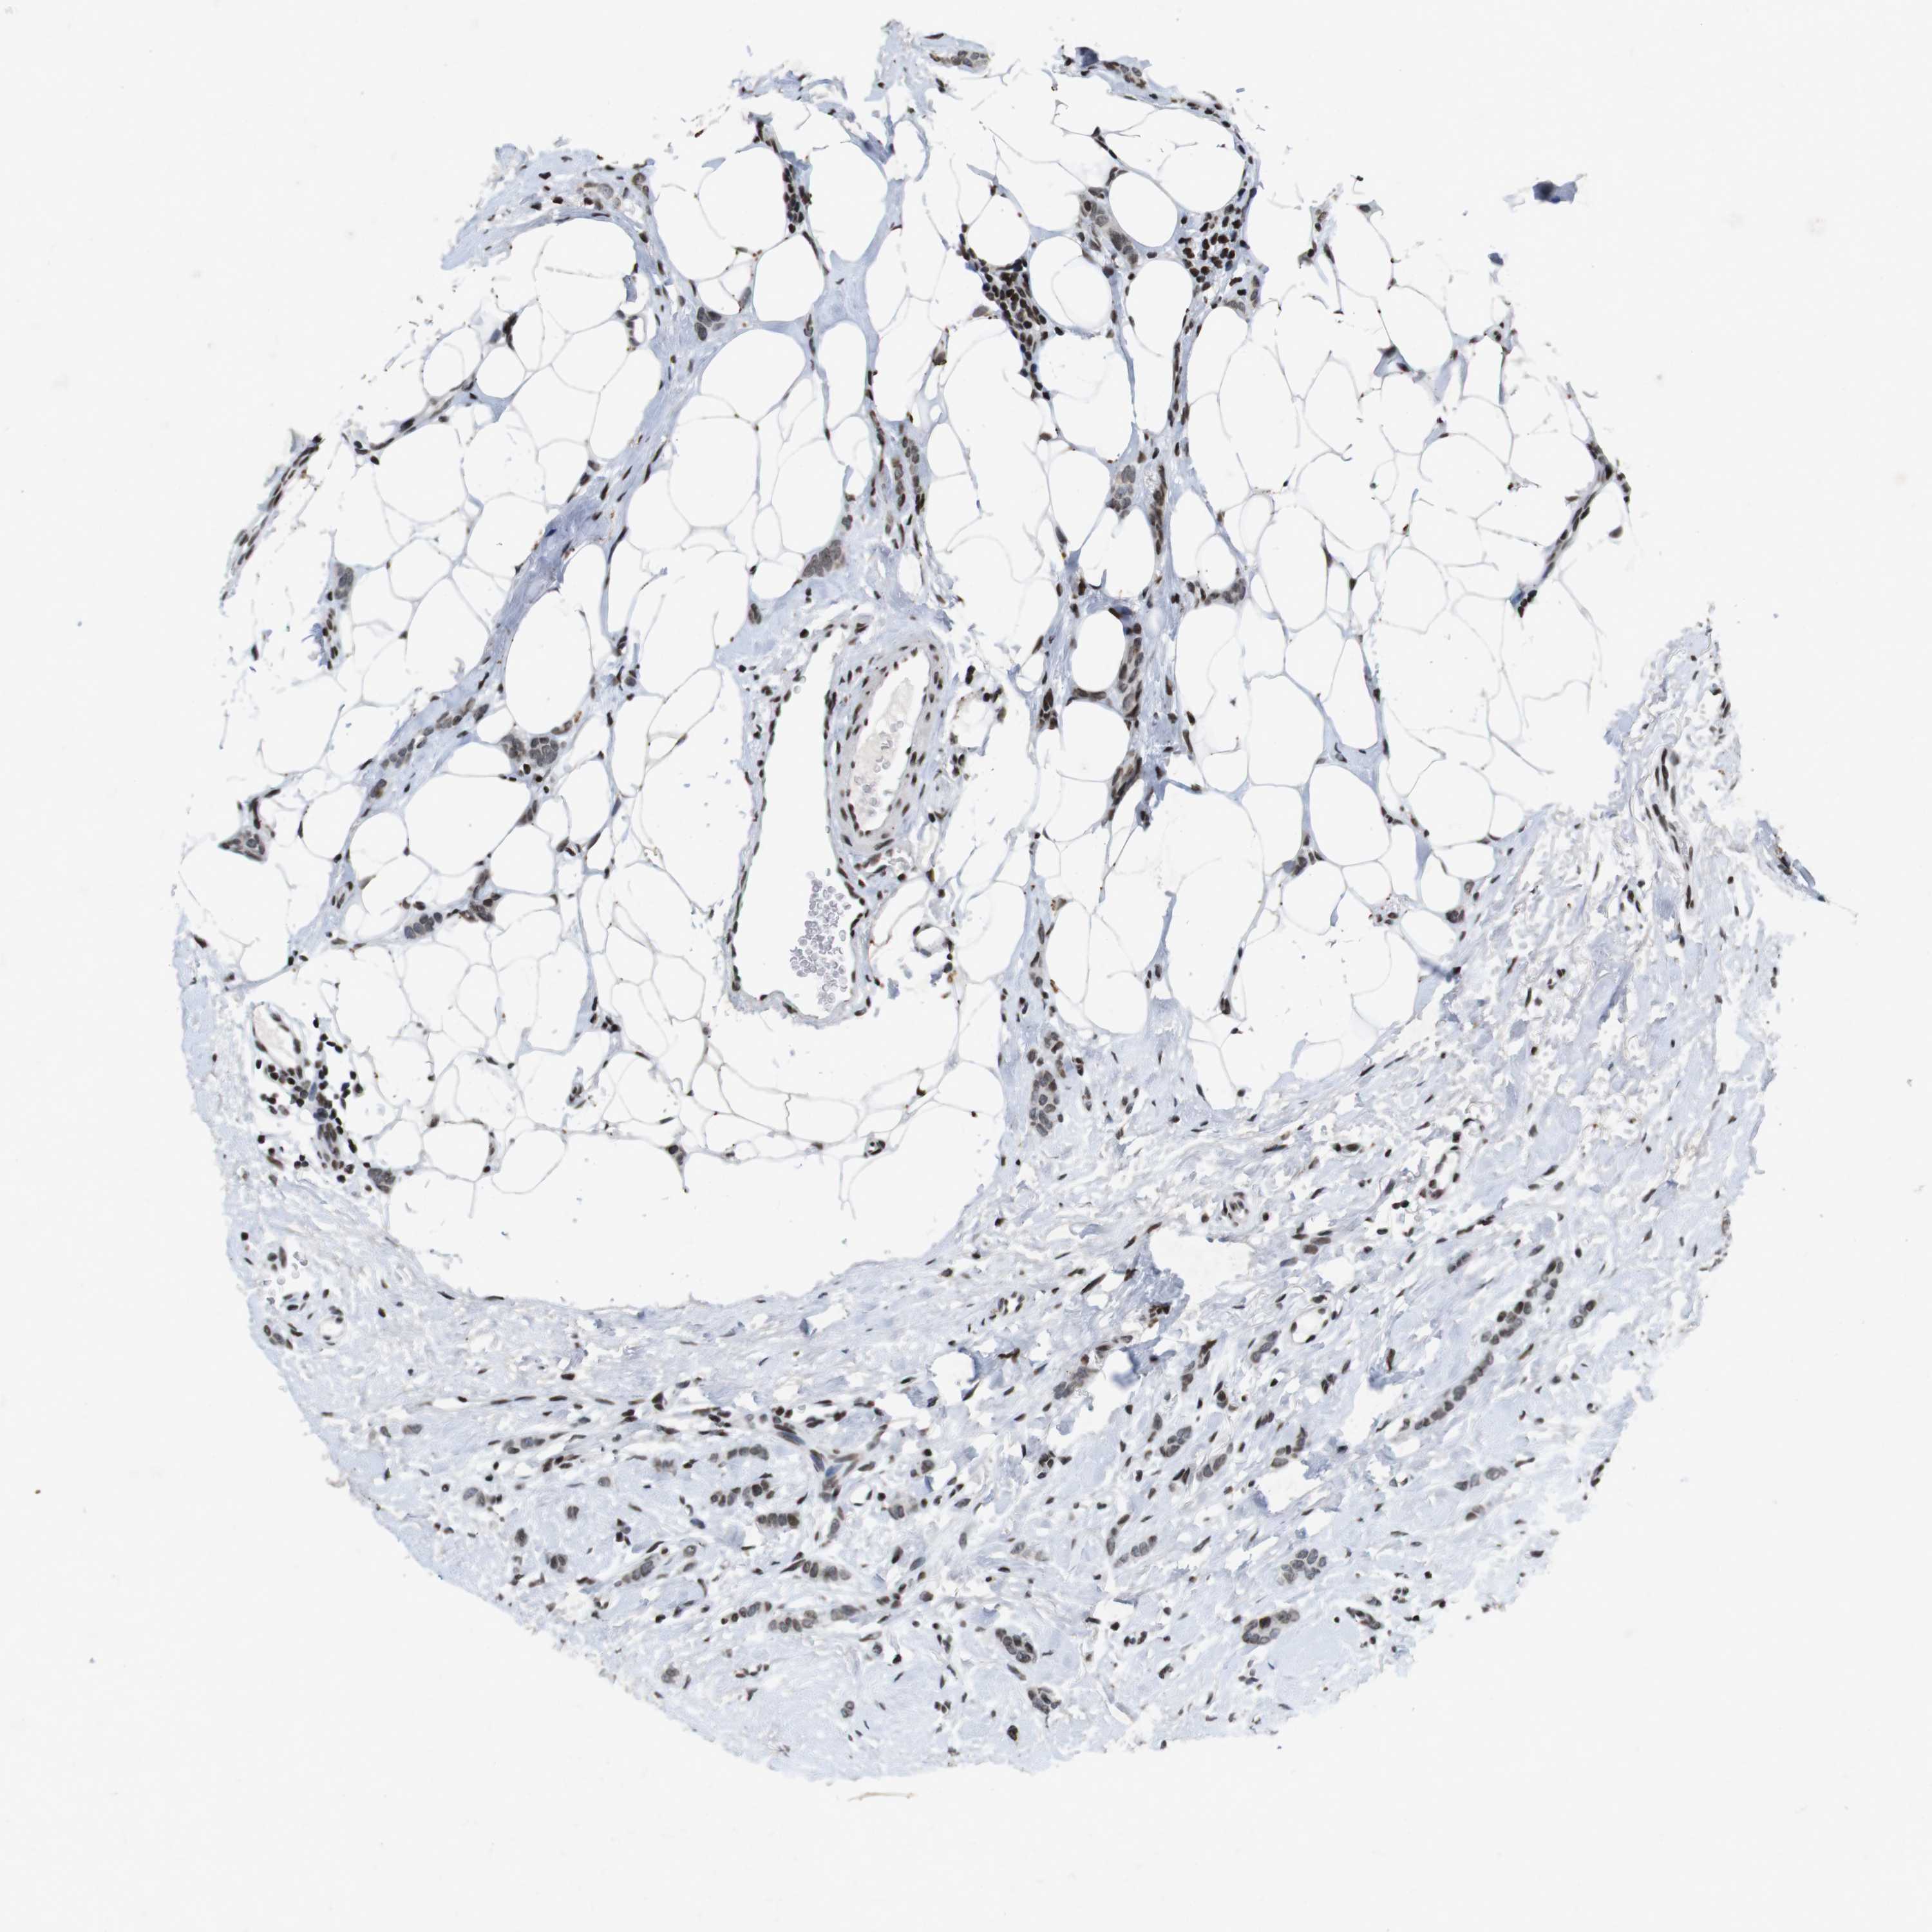

CANCER BREAST CANCER Show tissue menu

BRCA TCGA BRCA VALIDATION PROTEIN EXPRESSION